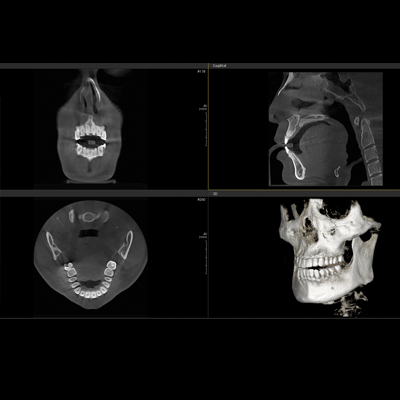

PAPAYA 3D

Diaqnostik kompyuterli erqonomik rentgen sistemi

-3D CT, Panorama

-Çoxsaylı -FOV seçimi (4×5, 14×14)

-Açıq yerləşdirmə (üzbə - üz)

-Çoxsaylı Fokuslanma

-70um görüntülü ENDO rejim